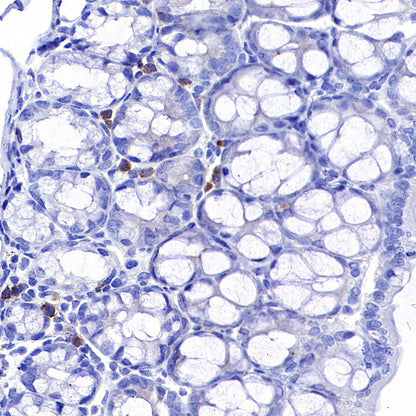

Immunohistochemistry

IHC shows positive staining in paraffin-embedded mouse thymus. Anti-CD8α antibody was used at 1/500 dilution, followed by a HRP Polymer for Mouse & Rabbit IgG (ready to use). Counterstained with hematoxylin. Heat mediated antigen retrieval with Tris/EDTA buffer pH9.0 was performed before commencing with IHC staining protocol.